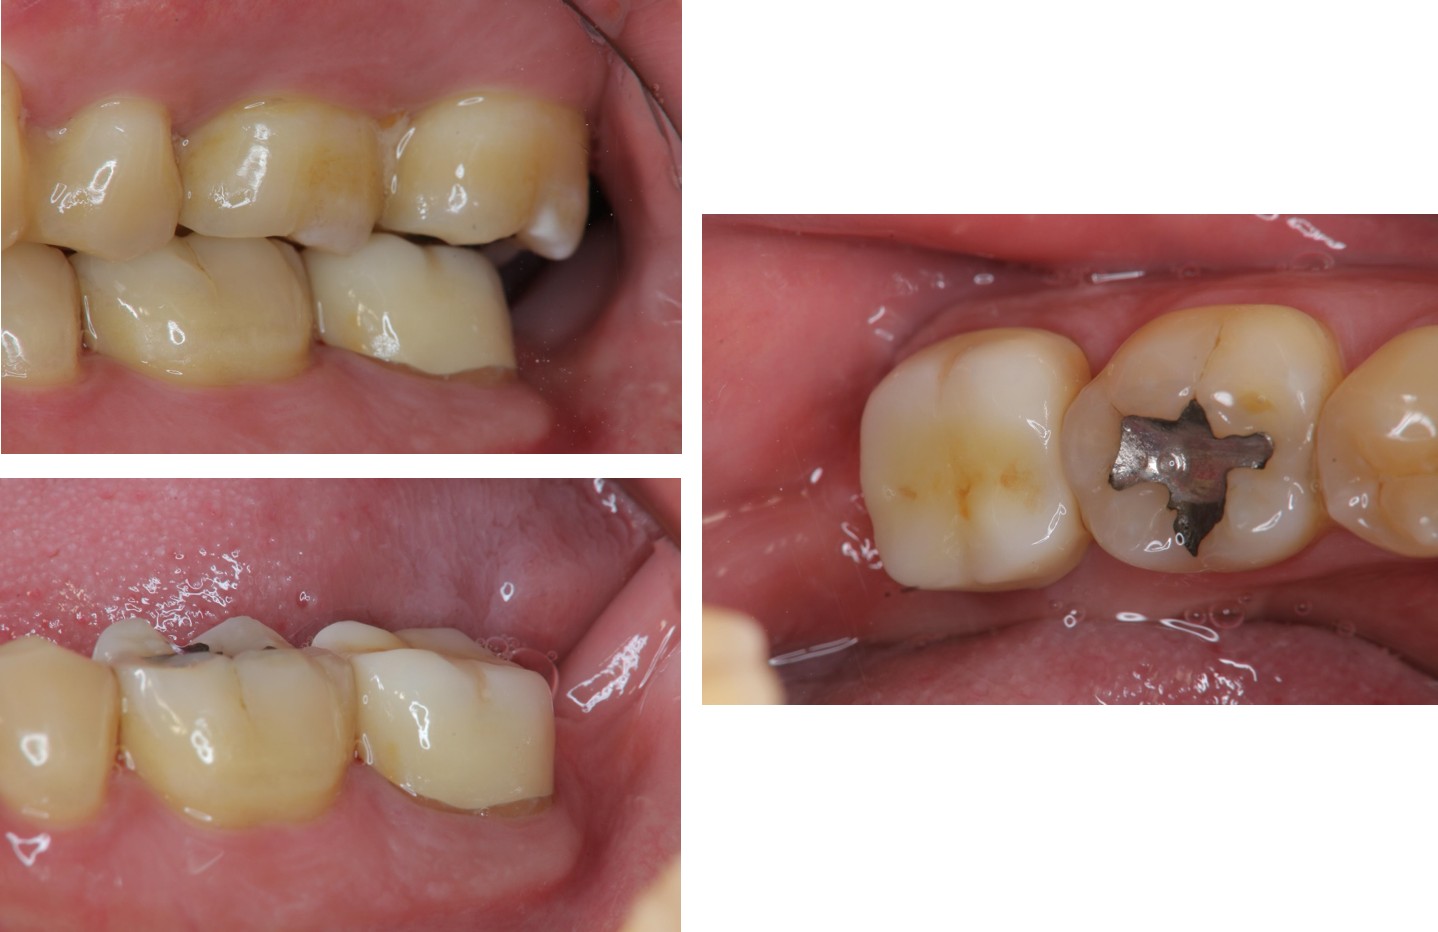

治療前,左下第二大臼齒疼痛

治療前,第二大臼齒有玻璃陶瓷全瓷冠

膺復前評估陶瓷斷裂處